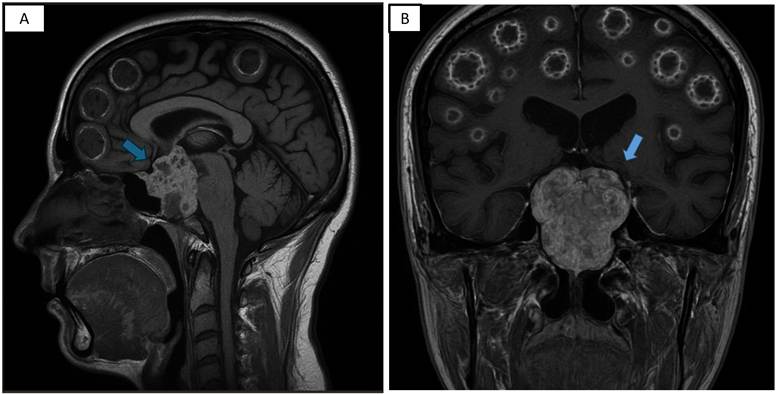

En la resonancia magnética (RMN) craneal se evidenció: adenohipófisis de 8x5x14 mm con reforzamiento heterogéneo posterior al contraste; engrosamiento heterogéneo de la silla turca y región petroclival con extensión a las regiones paraselares sugerente de macroadenoma hipofisiario. A nivel de calota, presencia de múltiples imágenes iso-hiperintensas en T1 y T2 que se refuerzan con el contraste de forma periférica y heterogénea, a considerar lesiones en sacabocado. (figura 1)

Figura 1: RMN craneal T1 sagital (A) y coronal (B): Adenohipófisis de 8x5x14 mm con reforzamiento heterogéneo posterior al contraste; engrosamiento heterogéneo de la silla turca y región petroclival con extensión a las regiones paraselares (flecha)